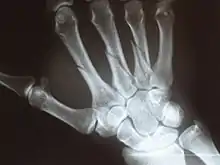

Multiple fractures of the metacarpals (aka broken hand). (Right hand shown with thumb on left.)